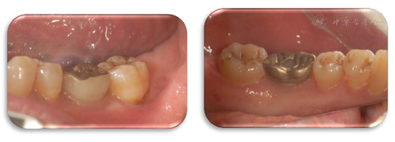

47叩痛(-),不松动,远中及颊侧中央PD7~9 mm,余位点PD3~4 mm,BI2-3,颊侧中央牙龈退缩约2 mm,无附着龈,舌侧牙龈无明显异常(图6,图7)。正中合未及早接触,侧方合未及合干扰,cbct示47颊侧及远中牙槽骨吸收超过根长2/3,颊侧骨缺损深约9 mm,宽约4 mm,远中骨缺损深约10 mm,宽约7 mm(图8,图9)